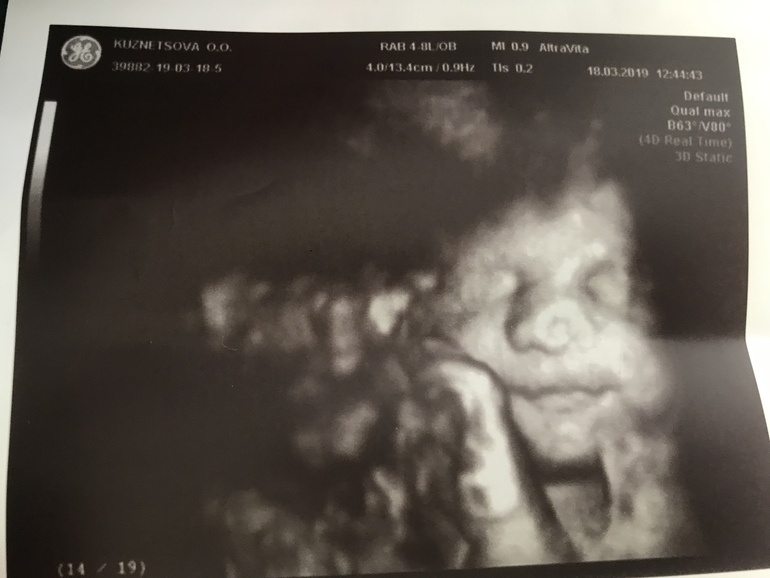

Вес 1901гр😍

Он много раз сказал, что это папина дочка (ресницы длинные, губы пухлые, головка большая)❤️ А волосы в маму «будет светлая шатенка, волосы кудрявенькие»😁

Пальчик сосала, потом губы трубочкой сложила, а он говорит «она плюётся!🤦🏻♀️😁 кто у тебя из сыновей ещё плюётся?». Я так подумала и отвечаю «средний», а он «так у тебя дети через одного плюются!»🙈😂

Спросил, как назвала. Я ответила «Арина», а он «не Родионовна?», я «нет, Валентиновна» - и она в этот момент улыбнулась 😊😍

Всё УЗИ была серьёзная, а тут улыбнулась... Моя принцесса 👑, моё солнышко ❤️